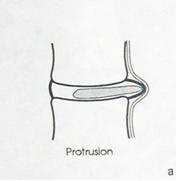

I стадия — протрузия диска — смещение в сторону позвоночного канала пульпозного ядра и выбухание в позвоночный канал элементов фиброзного кольца межпозвонкового диска без нарушения целостности последнего;

2 стадия — экструзия — выбухание в позвоночный канал элементов фиброзного кольца и дегенерированного пульпозного ядра;